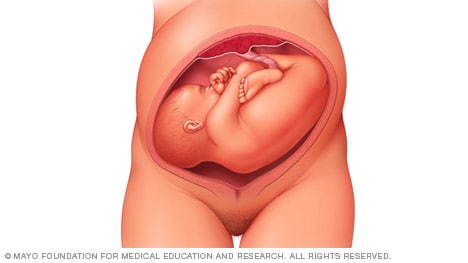

Complete and incomplete breech

A complete breech presentation, as shown below, is when the baby has both knees bent and both legs pulled close to the body. In an incomplete breech, one or both of the legs are not pulled close to the body, and one or both of the feet or knees are below the baby’s buttocks. If a baby is in either of these positions, you might feel kicking in the lower part of your belly.

If you are more than 36 weeks into your pregnancy and your baby is in a complete or incomplete breech presentation, your health care professional may try to move the baby into a head-down position. This is done using a procedure called external cephalic version. It involves one or two members of the health care team putting pressure on your belly with their hands to get the baby to roll into a head-down position.

If the procedure isn’t successful, or if the baby moves back into a breech position, talk with a member of your health care team about the choices you have for delivery. Many babies in a complete or incomplete breech position are born by planned C-section.